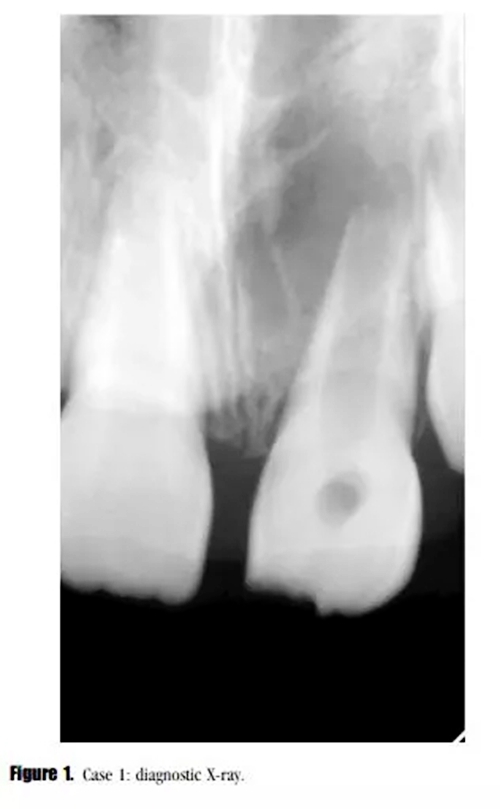

主訴:左上恒中切牙腫脹。(圖1)

影像學檢查: X線顯示,21根尖發(fā)育達到第三階段,根尖區(qū)被大面積低密度透射影像包繞?;佳辣辉\斷為慢性根尖周炎急性發(fā)作。